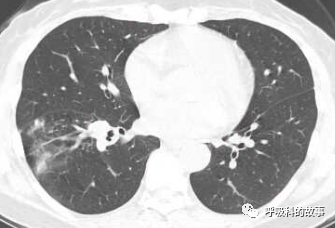

1個月前,黃女士來到了杭州市第一人民醫院呼吸科,找到我看病,我給她複查了肺部CT,如下:

初一看,好像就是普通的肺炎,可是為什麼相隔兩個月在同一部位反覆發生呢?另外,右下葉肺門較左側明顯增大,感覺到管腔似乎也不是那麼清爽,於是我繼續開啟縱隔窗繼續檢視影像情況。

這一看嚇我一跳,患者右下葉支氣管腔內有高密度影,這讓我首先想到的就是支氣管異物堵塞管腔,從而引起阻塞性肺炎。於是我在認真檢視後,嚴肅地對患者說要住院。黃女士可能一來工作繁忙,二來對我的診斷可能表示懷疑,因為她記憶裡沒有誤吸的事件發生,三來以前的CT報告也沒有提示支氣管異物,於是要求繼續口服藥物治療。